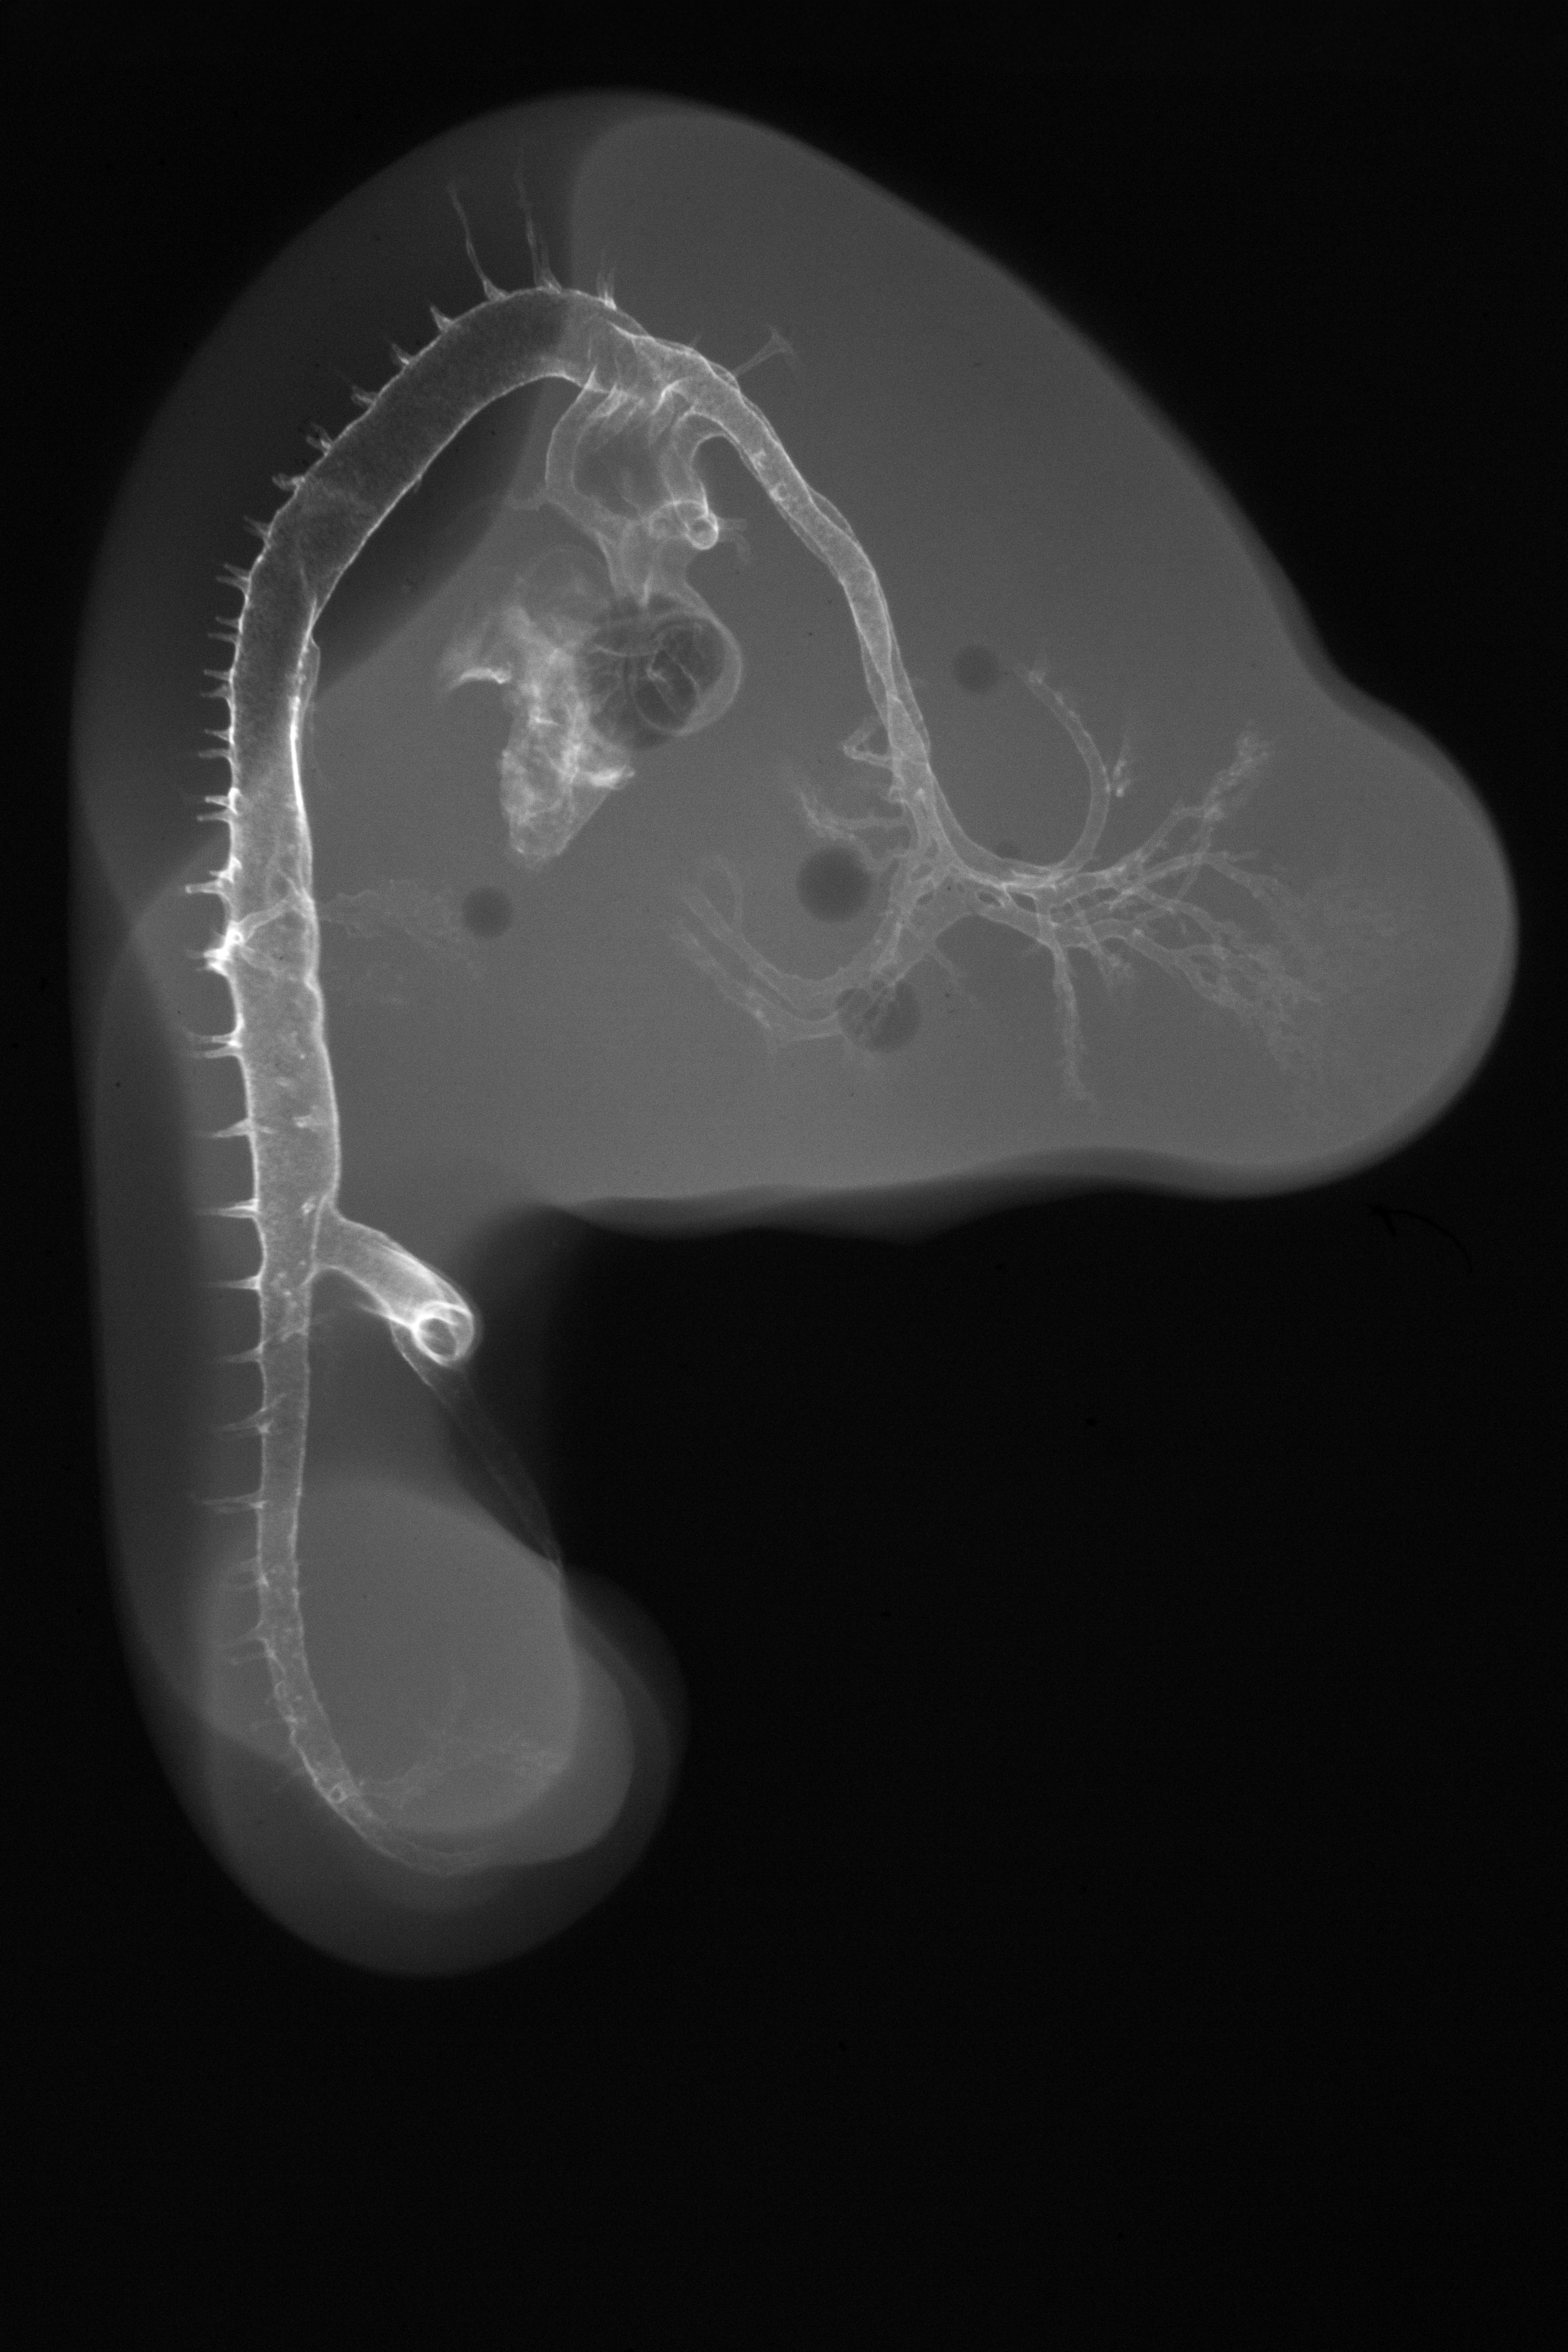

Chick Embryo Microangiography

Hamburger-Hamilton (HH) Stage 23 (approx. 4 days)

X-Ray Micrographs